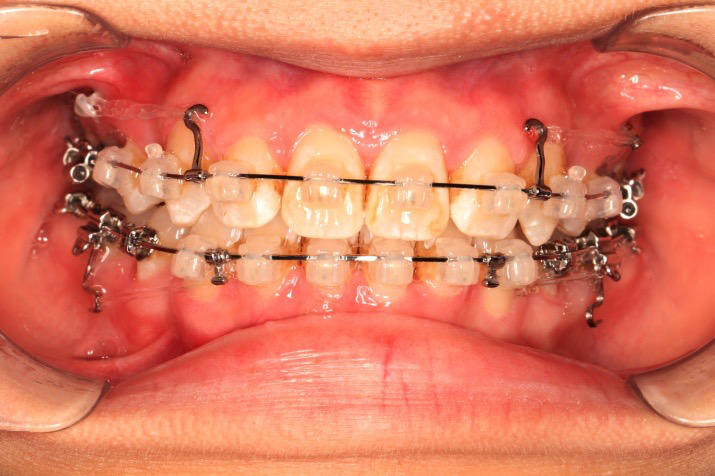

2018.11.14  术后磨牙尖牙I类关系,中线齐,覆合,覆盖正常

Post-TXPRE-TXPost-TXNormFMIA°47°57.555.0SNA°77.7°76.883.0SNB°70.2°73.780.0ANB°7.5°3.13.0FMA° 29.828.026PFH/AFH70.5°65.970Z Angle°50.3°64.477U1-FH113.0103.7110.0 IMPA°103.291.197.0U Lip tos’ line6.3 mm3.25.0L Lip to s’ line3.9 mm1.03.0OP-FH1212.615

牙根基本平行,未见牙根吸收